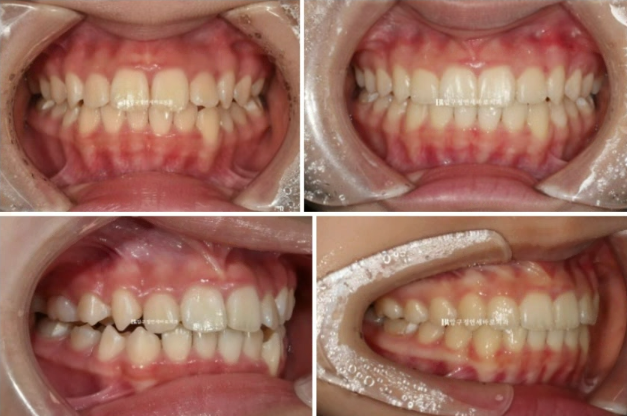

24.07

그리고 추가장치를 4달간 더 낀 후의 모습입니다.

중심선은 잘 맞아졌습니다.

교합도 좋습니다.

23.08~24.07

무엇보다 한쪽의 3급 어금니 교합관계는 1급이 되었습니다.

치료가 잘 끝났으니 1년간의 변화를 보겠습니다.

뿌리 평행도도 좋습니다.

22.12~24.07

어린이 교정에 있어서 소아교정의 한계를 설명하기 보다는 어린이 환자지만 성인때 교정을 안 해도 될만큼 완벽한 교합 만들기를 목표로 진료합니다.